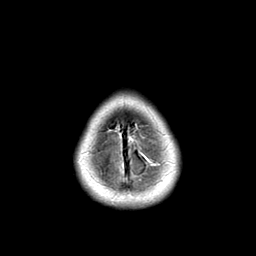

Metastatic bronchogenic carcinoma: T1-weighted MR -- Slice #22

[Home][Help][Clinical] Slice 22